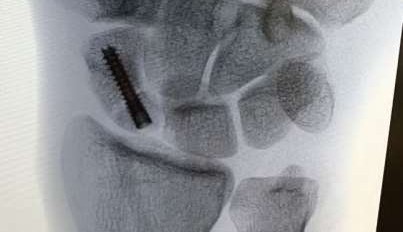

A 35-year-old woman reports wrist pain after a fall onto an outstretched hand. On exam, she has focal tenderness over the wrist snuffbox. A radiograph and CT image are shown in Figures A and B. What is the proper treatment of her injury?